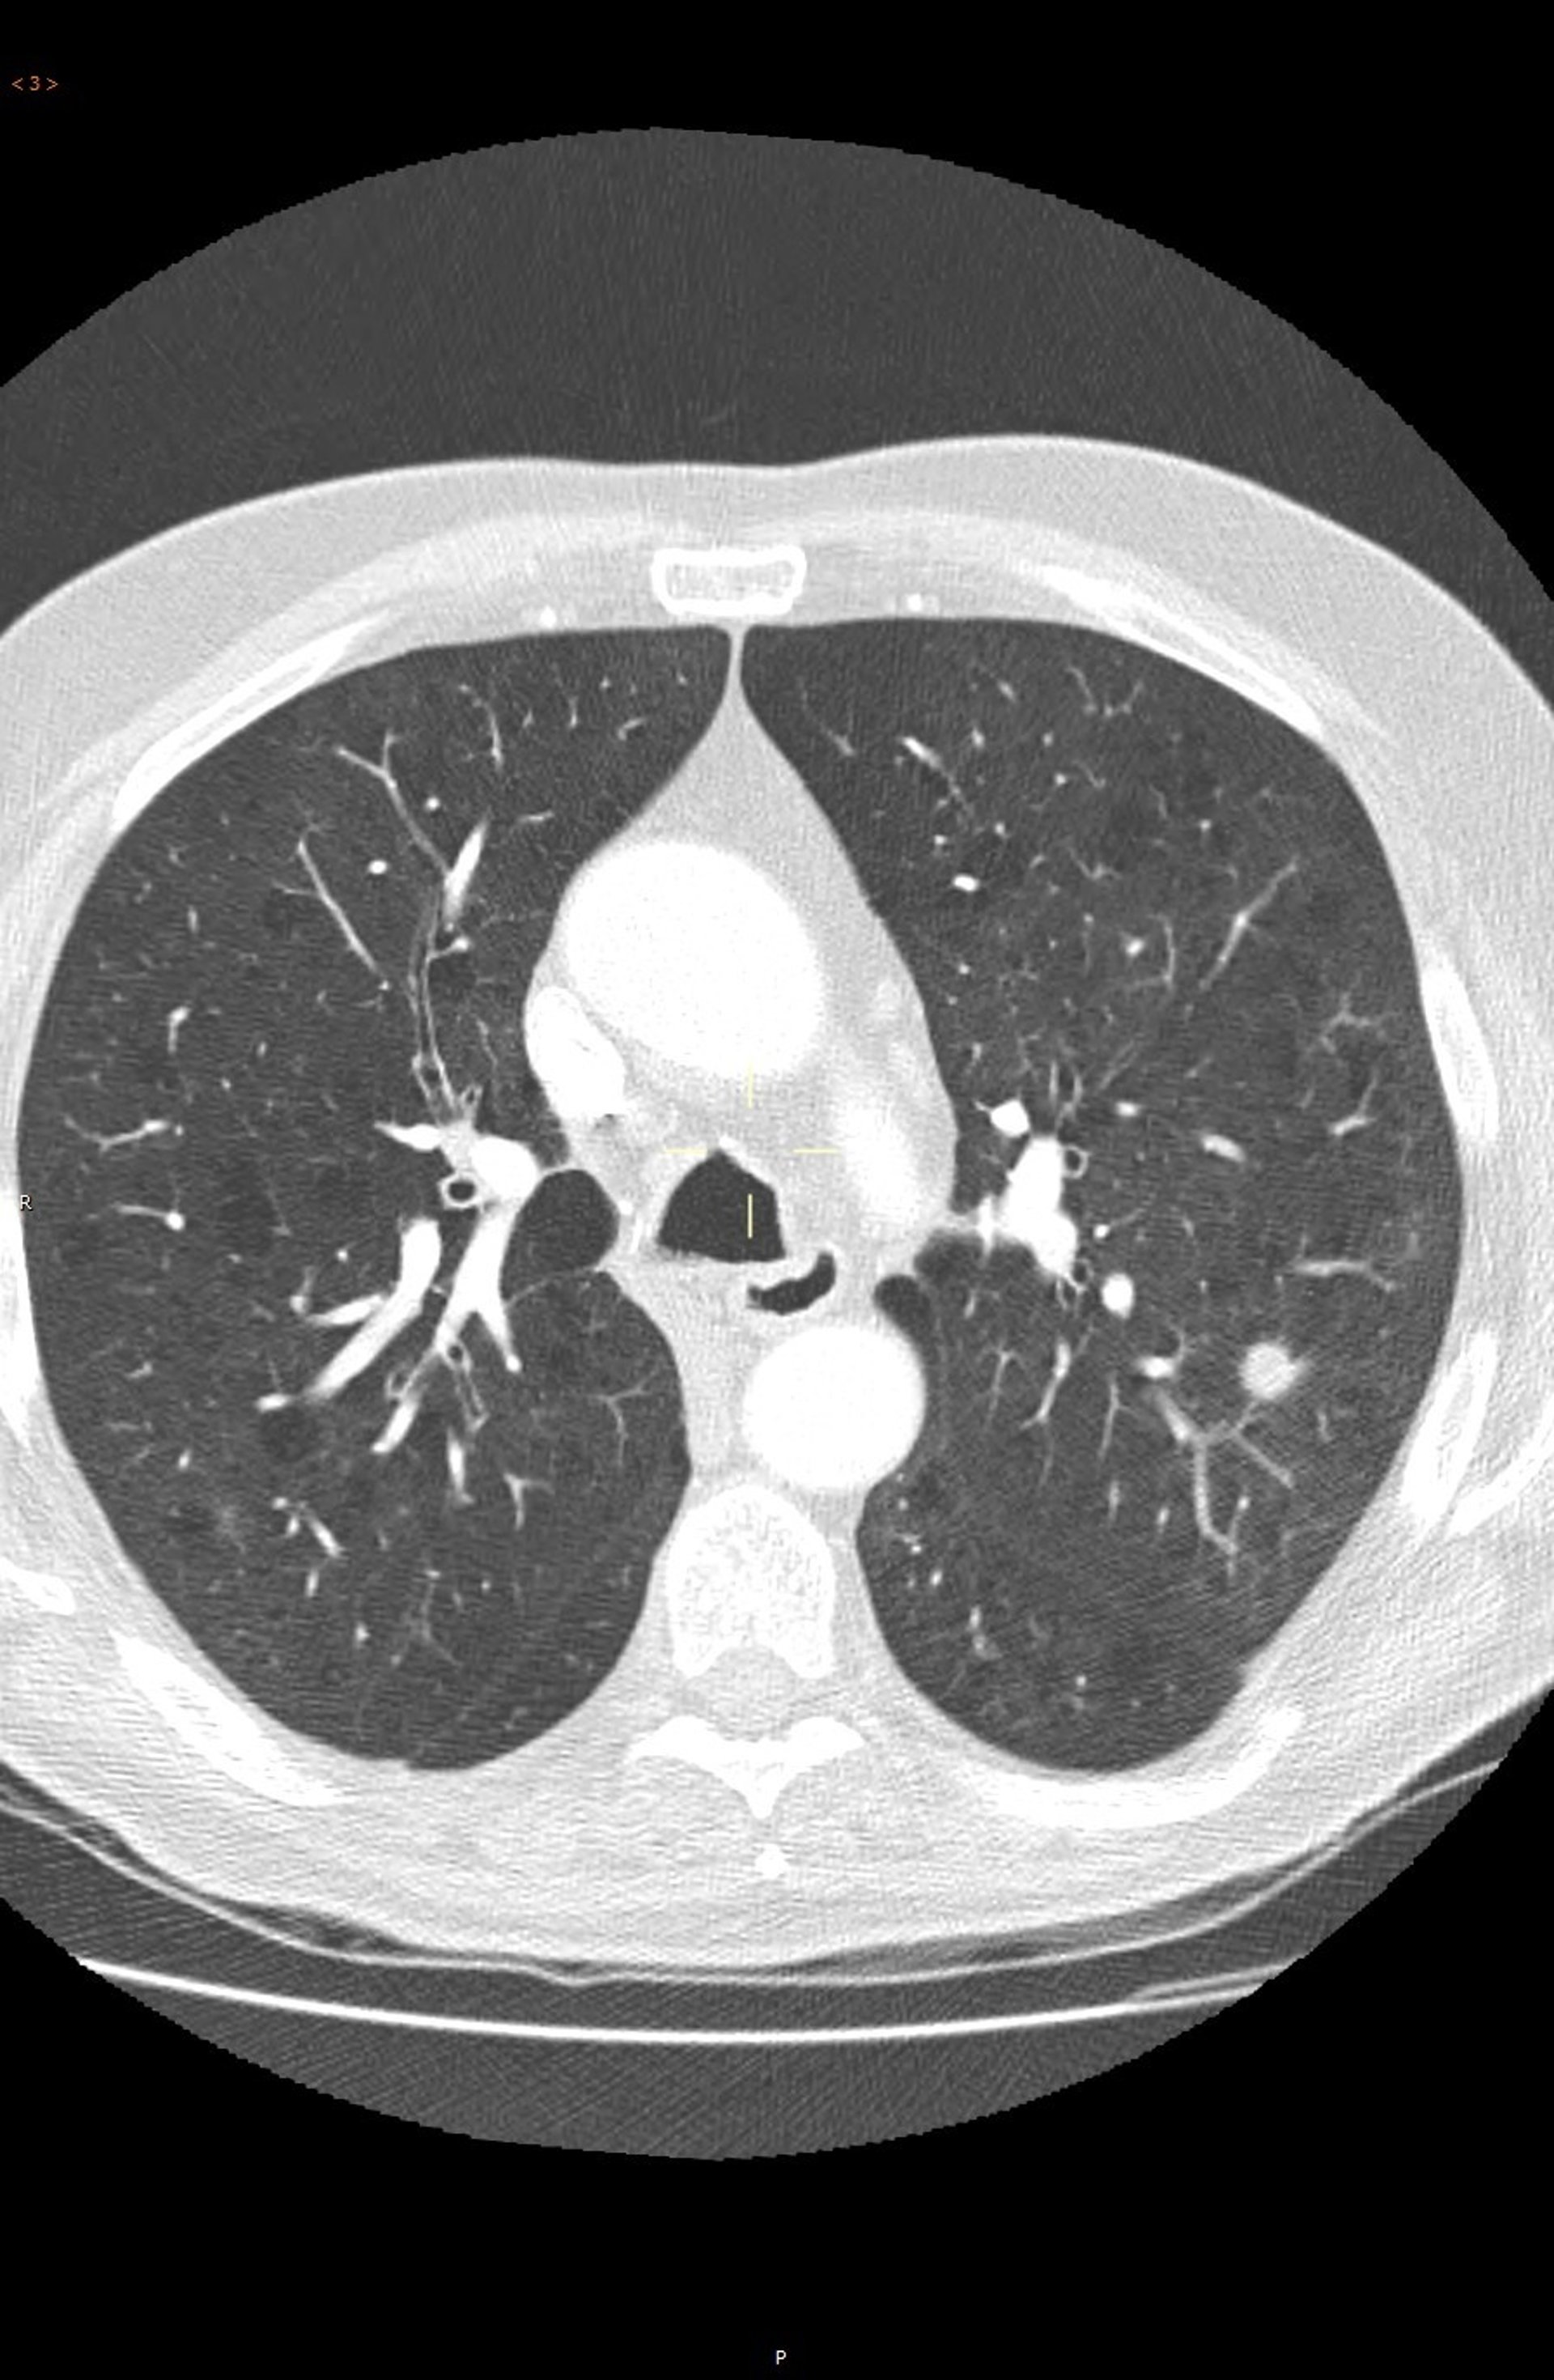

"El cáncer puede ser detectado en estadios más precoces utilizando la tomografía computarizada de baja radiación. Esta prueba permite identificar el cáncer en un estadio precoz, cuando se presenta en forma de un pequeño nódulo en el pulmón y antes de que se extienda a otras partes del cuerpo. Esta tecnología ha aumentado la tasa de curaciones", ha detallado el experto.

"El cribado con tomografía computarizada de baja radiación ha conseguido una detección de tumores en estadios precoces. En la actualidad sólo un 15 por ciento de los carcinomas no microcíticos de pulmón permiten una intervención curativa; mientras que en los programas de cribado mediante tomografía computarizada han conseguido la detección de entre un 65 y un 85 por ciento de tumores en estadios precoces", ha detallado Echave-Sustaeta, que considera que las personas que están en el grupo de alto riesgo de cáncer deberían realizarse la prueba una vez al año.